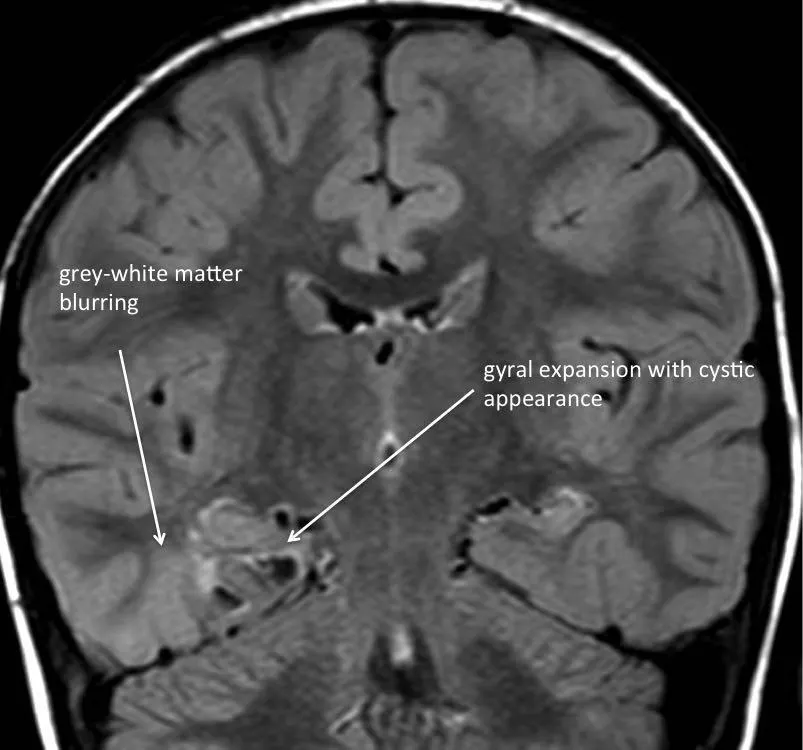

● 胚胎发育不良性神经上皮肿瘤

胚胎发育不良性神经上皮肿瘤是第二常见的胶质神经元肿瘤。典型表现为一种位于皮质基底的幕上病变,易累及颞叶,并伴有慢性局灶性癫痫。通常在CT或磁共振成像上既没有强化,也没有明显的占位效应或血管源性水肿。病灶表面的骨质可因长期压迫而呈扇形改变。约20%至30%的病例可见钙化。组织学上,胚胎发育不良性神经上皮肿瘤可能被误诊为少突胶质细胞瘤,因为前者含有类似少突胶质细胞的细胞。这些肿瘤的边界通常易于分辨,因此可以通过手术切除。部分切除的肿瘤进展率虽低,却可能与持续或复发的癫痫发作有关。对于进展性或复发性胚胎发育不良性神经上皮肿瘤,可以采用重复手术治疗,因此通常不需要辅助治疗。

胚胎发育不良性神经上皮肿瘤